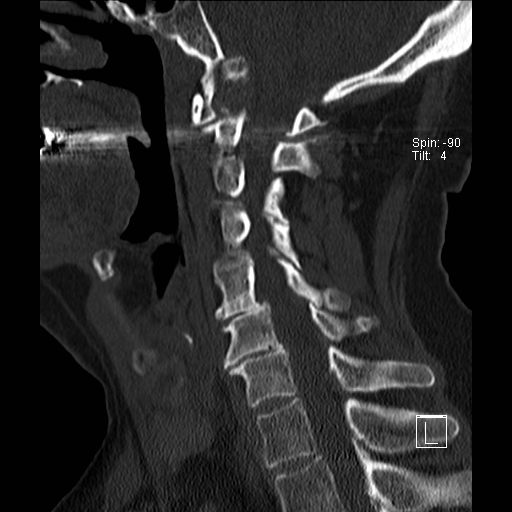

Lồng nền sọ

Lồng nền sọ, còn gọi là sụt lún sọ não hay ấn nền sọ, xảy ra ở 5-10% bệnh nhân viêm khớp dạng thấp cột sống cổ.

Trong lồng nền sọ, mỏm răng sa vào lỗ chẩm làm thu hẹp không gian dành cho tủy sống.

Biểu hiện lâm sàng đa dạng, từ đau đầu mạn tính, hạn chế vận động cổ đến suy giảm thần kinh cấp tính (chèn ép tủy sống và thân não, có thể dẫn đến liệt hoặc thậm chí tử vong nếu cổ bị di chuyển ở một số tư thế nhất định).

Hình ảnh

Cuộn xem các lát cắt CT.

Có hình ảnh di chuyển lên trên của mỏm răng vào lỗ chẩm.